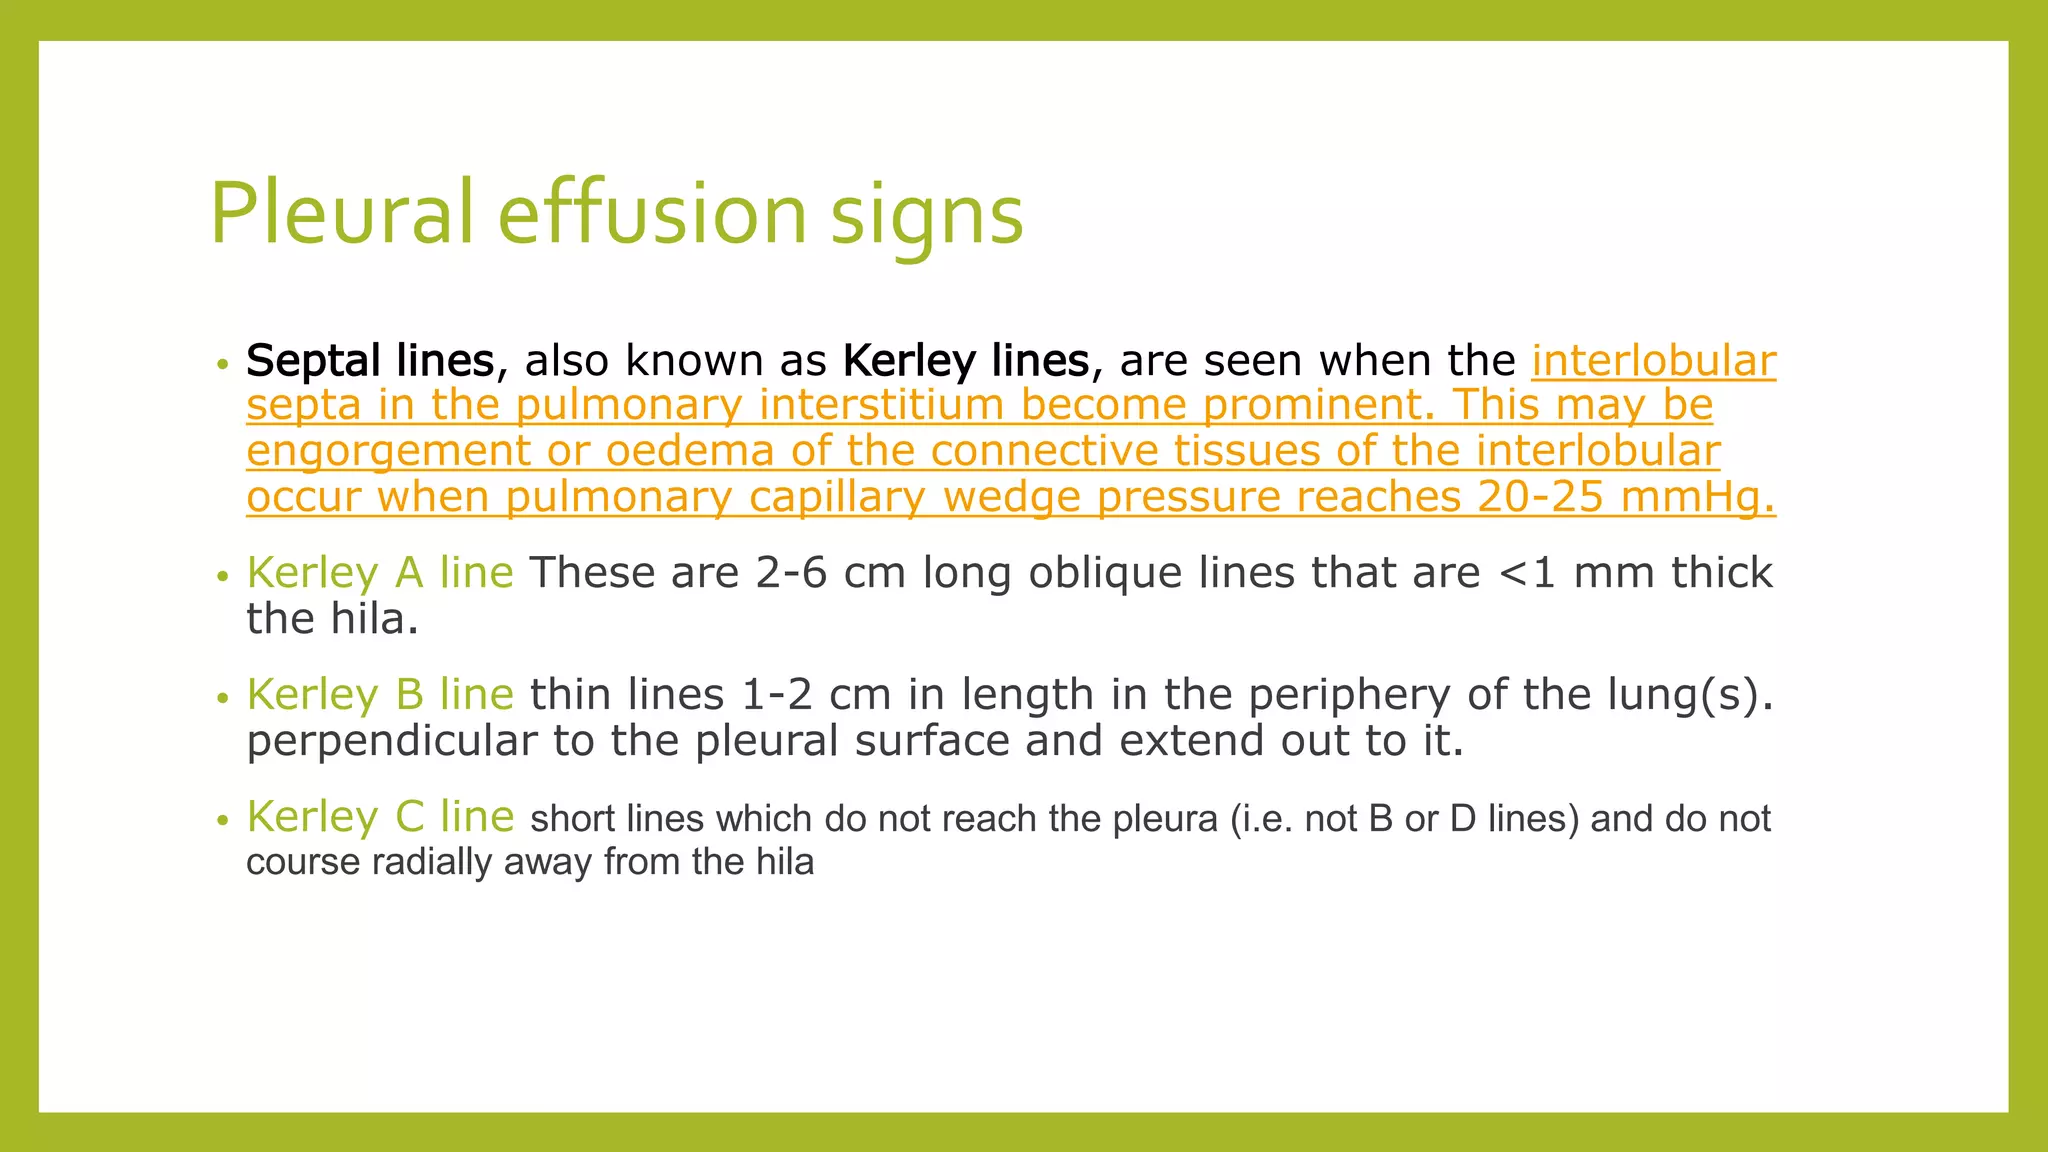

The document provides guidance on approaching and interpreting chest x-rays (CXR). It outlines steps to check the name, date and quality of the film, systematically scan the CXR looking for abnormalities, and determine if the lungs appear too white or black. Specific signs are described to help localize abnormalities, including the cardiac silhouette sign and pleural effusion signs. Examples are given of respiratory distress syndrome, tetralogy of fallot, transposition of great arteries, and total anomalous pulmonary venous return. The take home message is to summarize positive findings, compare to prior CXRs if available, and confirm findings with a radiologist.